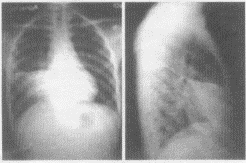

2.患者行胸片正側位檢查,胸片圖像表現如下,你認為該患者應首先考慮哪些疾病

A.右肺中葉大葉性肺炎

B.右肺中葉肺癌

C.右肺中葉支氣管擴張

D.右肺中葉結核

E.右肺中葉腺瘤

D.右中下肺野形成一片密度增高的陰影,與右心緣相連,其上緣銳利平直,由此向下逐漸變淡,移行至正常透亮的肺野,肋膈角清晰

E.側位片上呈三角形,尖端指向肺門,底部緊接前胸壁或肋膈角,上緣以橫裂為界,下緣為斜裂的前半部